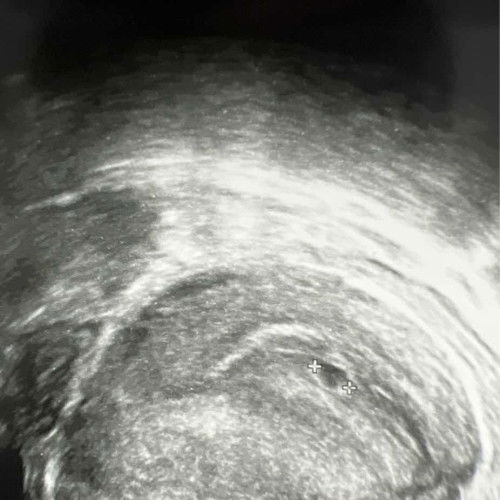

5 weeks 3days transvaginal scan

How to see if there is yolk sac? Is the image above shows there is yolk sac already? #firsttimemom #advice #firstmom #obgyn

the small tiny dot in the big circle is the yolk sac. im at 5 weeks, 1 day, recently NUH A&E couldnt find my yolk sac until gynae did 3rd scan then the yolk can see properly.